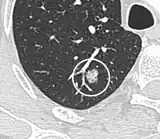

If there is an intermediate risk of malignancy, further imaging with positron emission tomography (PET scan) is appropriate (if available). It can be done simultaneously as a CT scan in the form of PET-CT. Around 95% of patients with a malignant nodule will have an abnormal PET scan, while around 78% of patients with a benign nodule will look normal on PET (this is the test sensitivity and specificity).[15] Thus, an abnormal PET scan will reliably pick up cancer, but several other types of nodules (inflammatory or infectious, for example) will also show up on a PET scan. If the nodule has a diameter of less than one centimeter, PET scans are often avoided because of an increased risk of falsely normal results.[15][16][17] Cancerous lesions usually have a high metabolism on PET, as demonstrated by their high uptake of FDG (a radioactive sugar).

-

PET-CT of a tuberculoma.